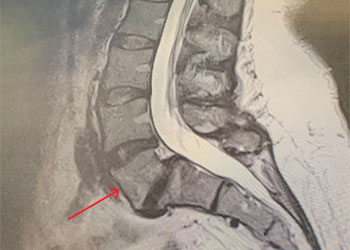

MRI of the lumbar spine (Fig. 1) demonstrated a grade 1-2 spondylolisthesis at L5-S1 with bilateral pars defects with significant L5-S1 foraminal compression. She had an […]